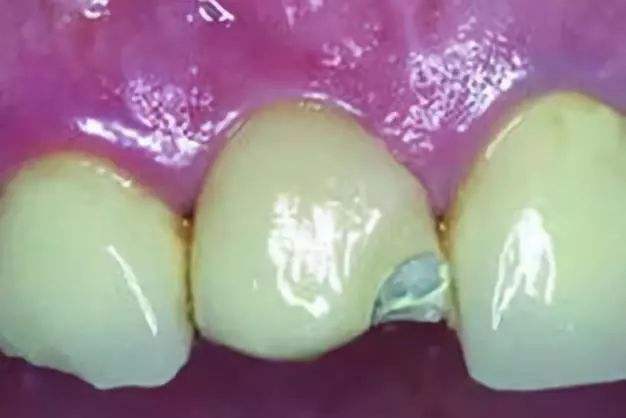

引起牙龈黑线的

这种也是佩戴烤瓷牙(镍铬合金、钴铬合金等)后最常出现的情况,因其价格低廉在当时备受欢迎,但是在长期的佩戴过程中会出现牙龈发黑的现象,这是因为非贵金属烤瓷牙在口腔内氧化成灰色氧化物,时间久了沉淀于牙龈,造成牙龈黑线,若不及时拆除,很可能会出现牙龈炎、牙周炎甚至牙齿脱落。

烤瓷牙崩瓷

选择什么样的加工厂,患者是否粗暴对待烤瓷牙?用用就知道了,崩了会怎么样?崩瓷边缘较尖锐,会造成舌头,唇部粘膜创伤,而且崩瓷后金属外露,在长时间的食物摩擦及唾液的作用下发生化学反应,那就一个字,拆!